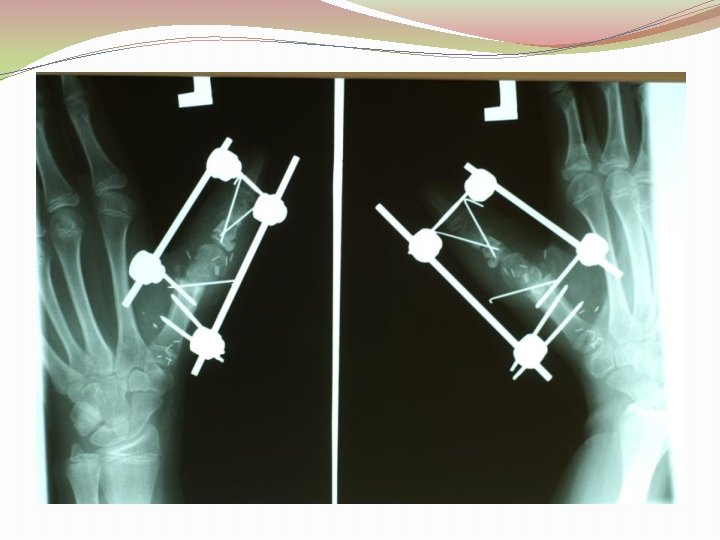

Ķirurģiska ārstēšana Osteomielīta pacientiem jāveic radikāls debridement ķirurģiski, kas ietver visu procesā iesaistīto audu rezekciju: �Mīksto audu rētas rezekcija �Cīpslu kalcinātu rezekcija �Distantu sekvestru rezekcija �Kaula rezekcija līdz vizuāli veseliem audiem – readzama punktveida asiņošana ´Paprika sign’. Bogdan Maciuceanu, Lucian Jiga, Alexandru Nistor, Jenel Marian Pastrascu, Mihail Ionac Chronic Osteomyelitis of Long Bones Timisoaral Medical Jornal, 2005

Ķirurģiska ārstēšana Veiksmīgas ķirurģiskas ārstēšanas stūrakmens ir mirušas telpas ‘Dead space’ aizpildīšana, kas izveidojas pēc debridemet veikšanas Brad Parsons, Elton Strauss, Surgical management of chronic osteomyelitis, The American Journal of Surgery 188 (Suppl to July 2004) 57 S– 66 S

Debridement Os konstrukciju evakuācija Biopsija un mikrobioloģija Dobuma slēgšana Antibakteriāla terapija Stabilizācija (Ārējā fiksācijas aparāts) Maina vai apstiprina antibakteriālo terapiju Mīksto audu rekonstrukcija 6 nedēļas antibakteriāla terapija (pēc debridement) Pseidartroze Konsolidācija Atkārtot ārstēšanu Luca Lazzarini, Jan T. Mader, Joson H. Calhaun Osteomielitis in Long Bone, The journal of bone&joint surgery, Volume 86 A, nr 10, 2004